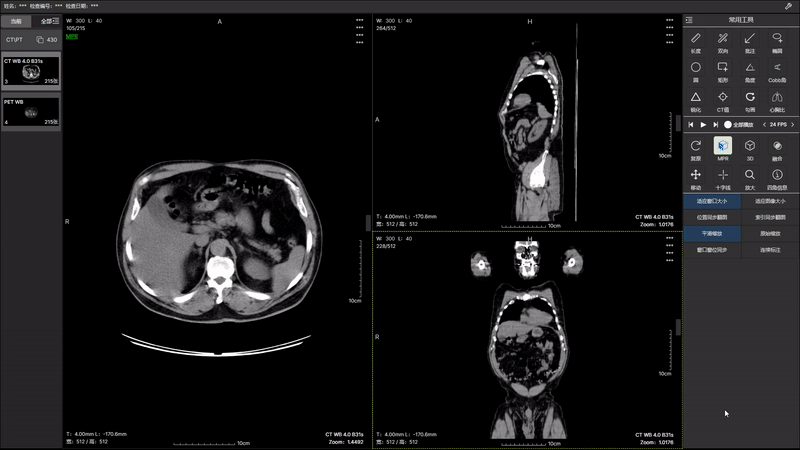

通过先进的算法和技术,我们在 2.0 版本中实现了 PT(正电子发射断层扫描)和 CT(计算机断层扫描)图像的无缝融合。这项突破性技术将为医生提供更全面、 更立体的患者图像,并且2.0 版本的图像融合带来了更高的分辨率和更丰富的图像细节。医生能够更准确地识别病变、评估组织状态,提高诊断的灵敏性和特异性, 为患者制定个性化的治疗方案提供更强有力的支持。医生可以更轻松地导航和比对 PT 和 CT 图像,提高工作效率。智能化的界面设计使操作更直观。 升级你的医学影像诊断体验,与 PT CT 图像融合 2.0 版本一同开启医学影像新时代。提升准确性,优化工作流程,为患者提供更全面的医疗服务。